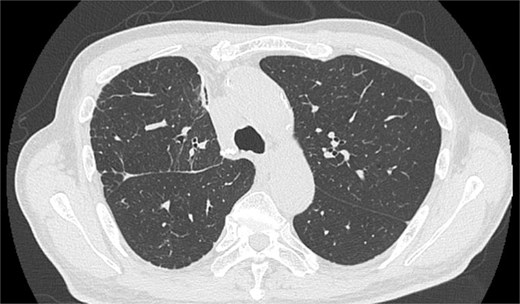

A man in his 70s presented for evaluation of a lung nodule on follow-up computed tomography (CT) 1 year postsurgery for early gastric adenocarcinoma. He had a history of heavy smoking (1.5 packs per day for 50 years) and had quit 1 year prior. CT revealed a 1.5 cm irregularly marginated solid nodule in the apical segment of the right upper lobe (Fig. 1a). Positron emission tomography (PET) revealed a maximum standard uptake value of 4.6 on the nodule (Fig. 1b). PET and brain magnetic resonance imaging revealed no metastases. All tested serum tumour marker values were within normal ranges. CT revealed emphysema of the lung. Pulmonary function tests indicated a forced expiratory volume in 1 s (FEV1.0) of 2130 ml and an FEV1.0/forced vital capacity ratio (FEV1.0%) of 65.3%. Bronchoscopic biopsy was not performed owing to difficulty in obtaining an informative specimen, and the lesion was suspected to be primary lung cancer. Although the size and location of the nodule met the criteria for intentional limited resection to treat lung cancer [3], lobectomy was considered more appropriate than apical segmentectomy for a sufficient margin and tolerable pulmonary function.

On POD 6, SE developed and spread to the chest, neck, and face. CT demonstrated remarkable mediastinal and SE with minimal lung collapse (Fig. 2; Video 2). Therefore, a chest tube was inserted, but minimal AL occurred from the chest tube, and the emphysema worsened. On POD 11, we performed thoracoscopic exploration and therapeutic intervention. Dense adhesion was confirmed between the staples on the interlobular plane and the dissected upper mediastinum. These were released, revealing the previous pleural tear. No other causative factors were observed. CT and operative findings suggested late-onset AL into the dissected mediastinum through dense adhesions. A leak test under positive pressure of up to 20 cmH2O revealed no AL from the pleural tear. The tear was sealed using a PGA sheet and fibrin glue, and 130 ml of autologous blood was injected into the pleural space to seal the dissected mediastinum and prevent air inflow (Video 3).

Image of postoperative mediastinal and SE with little lung collapse.